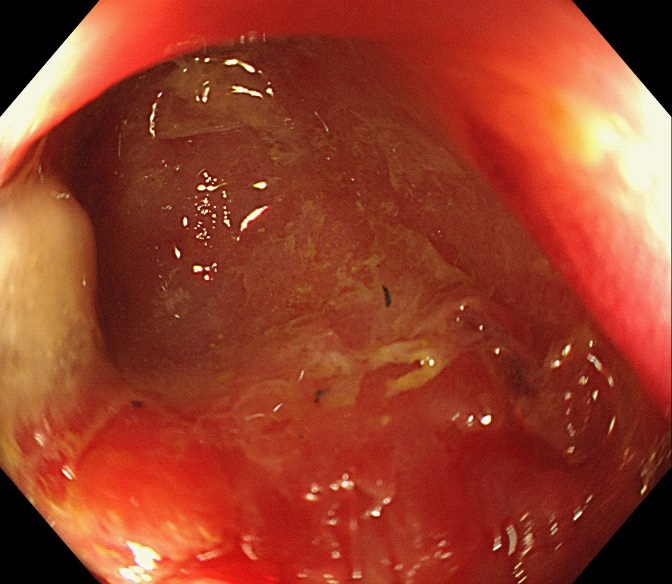

Figure 1: The computed tomography scan of abdomen showed about 20 mm X 20 mm circular high density shadow in right colon.

The computed tomography scan of abdomen showed about 20 mm X 20 mm circular high density shadow in right colon, which can be observed in colonic lumen but protruding out of the lumen. Colonoscopy (Figure 3) was also performed and the fecal impaction was identified in the cecal diverticulum above the ileocecal valve. The mucosa surrounding the diverticulum was hyperemic and edema. Than the fecalith was removed successfully with a foreign forceps under colonoscopy. The internal mucosa of the diverticulum was hyperemia, and no perforation was observed (Figure 4). The patient’s abdominal pain were relieved after endoscopic treatment. To prevent recurrence of the disease, surgical removal of the diverticulum was recommended but the patient was hesitant. There was no recurrence of abdominal pain and fecal impaction during 10 months follow-up.